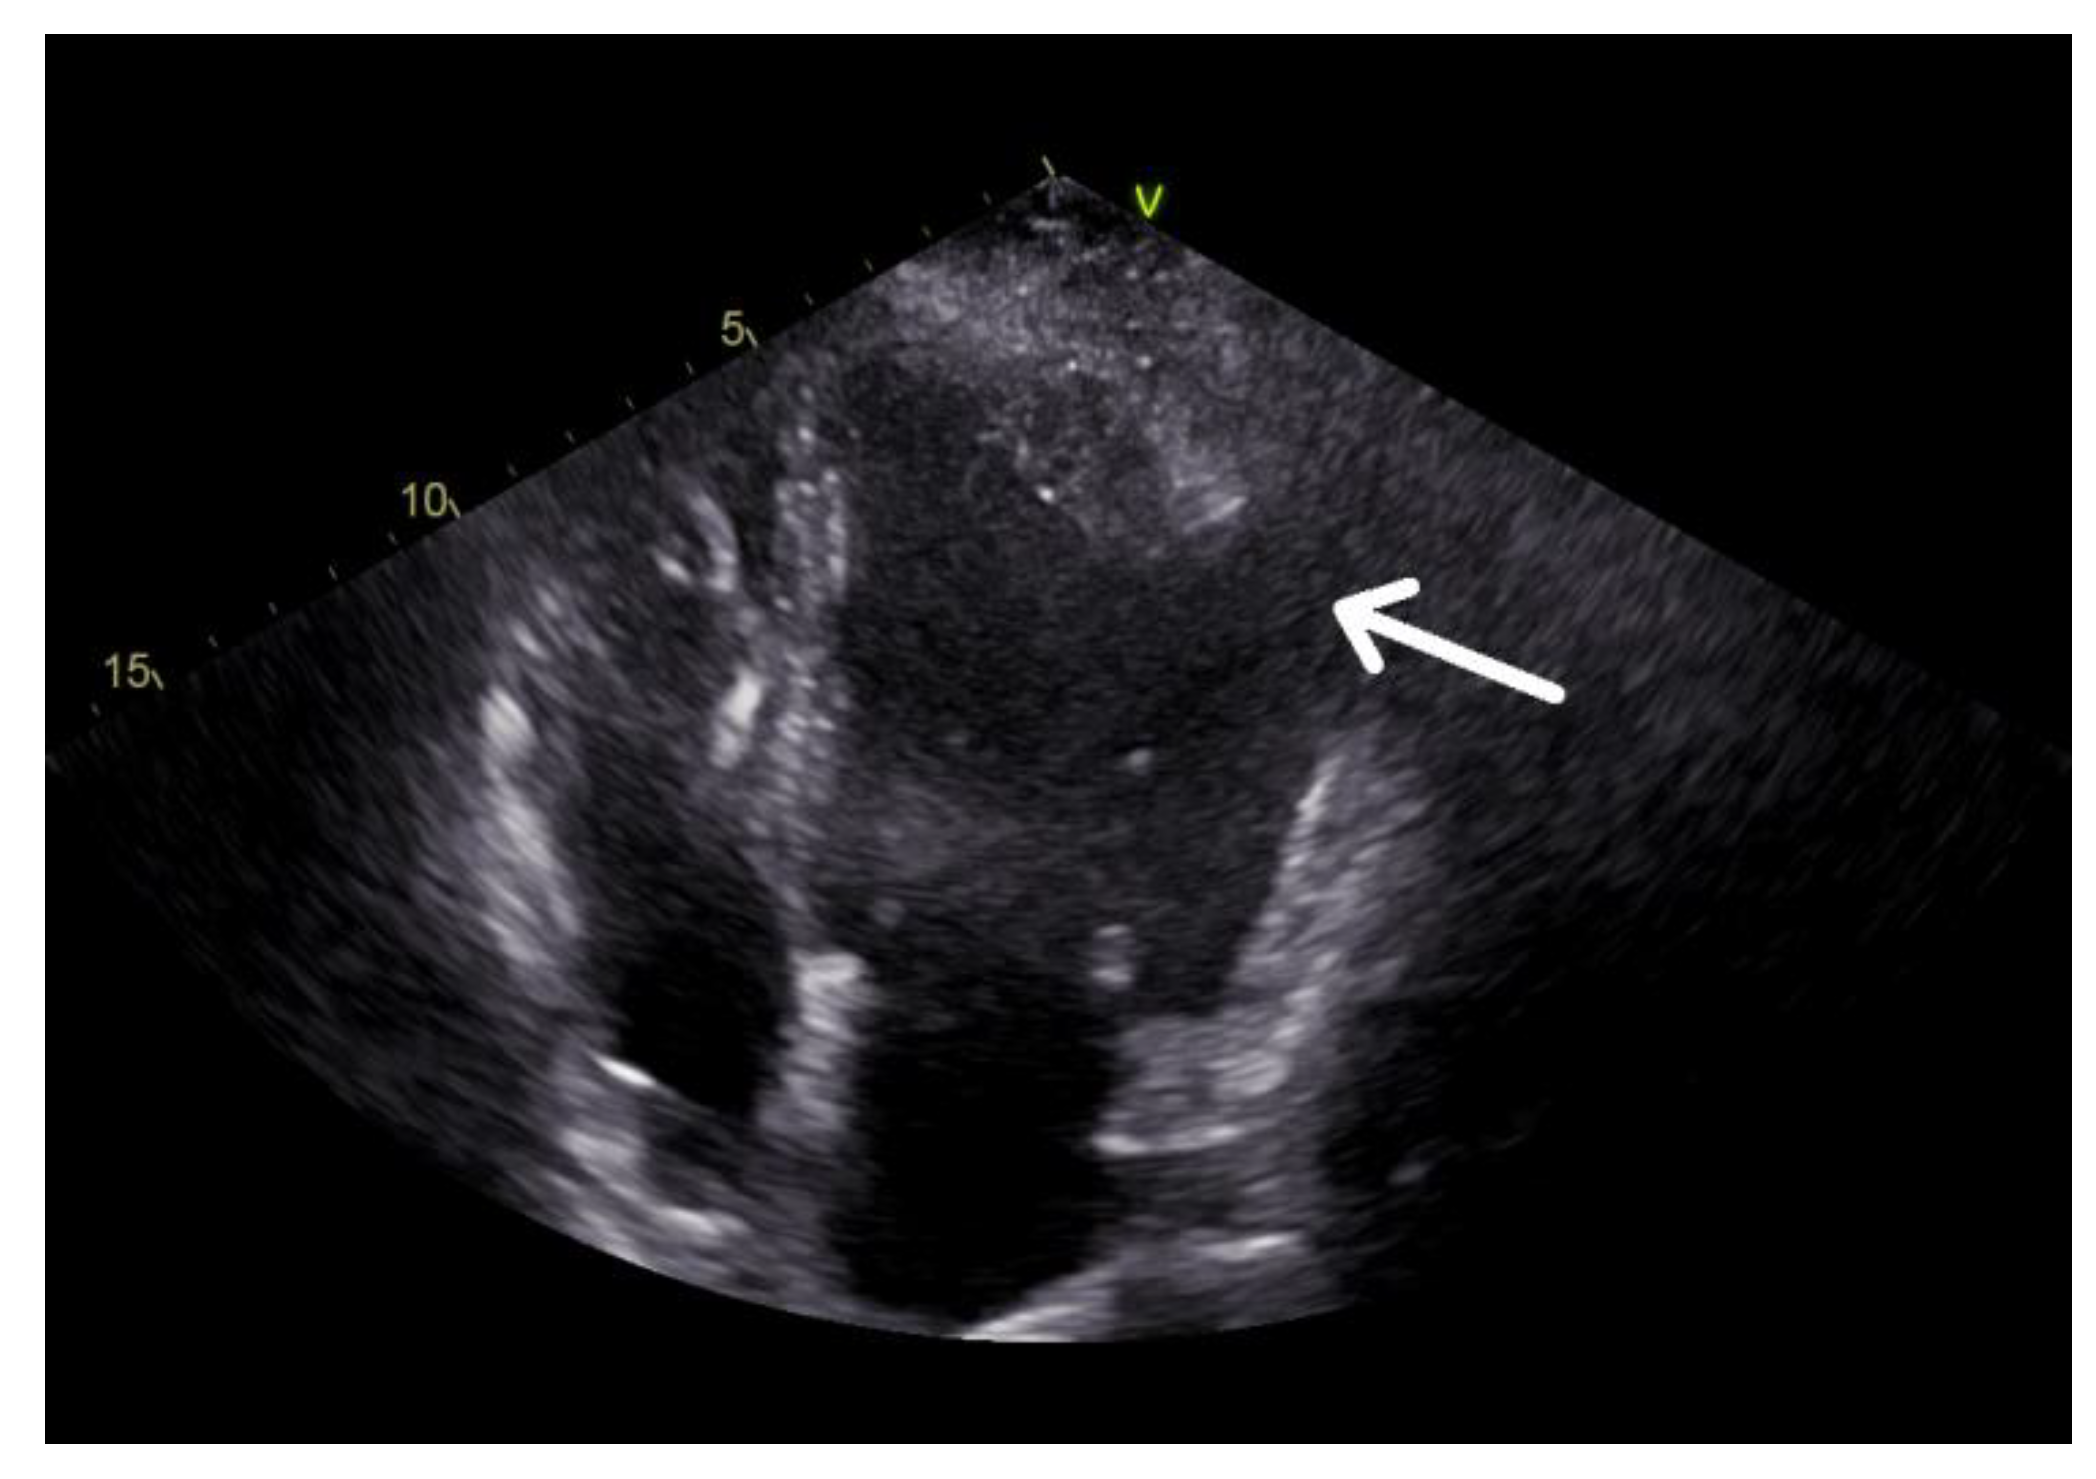

- Yang, C.H.; Wu VC, C.; Hung, K.C.; Lin, F.C. Early Detection of Left Ventricular Diverticulum by Transthoracic Echocardiography. J. Med. Ultrasound 2017, 25, 232–234. [Google Scholar] [CrossRef]

- Cianciulli, T.F.; del Carmen Gonzales Colaso, P.; Saccheri, M.C.; Lax, J.A.; Redruello, H.J.; Guerra, J.E.; Precioso, H.A.; Vidal, L.A. Left ventricular diverticulum, a rare echocardiographic finding: Two adult patients and review of the literature. Cardiol. J. 2009, 16, 76–81. [Google Scholar] [PubMed]